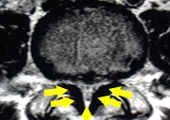

椎間板ヘルニアのMRI画像。前方の椎間板から脊柱管に向かってヘルニアが突出している。